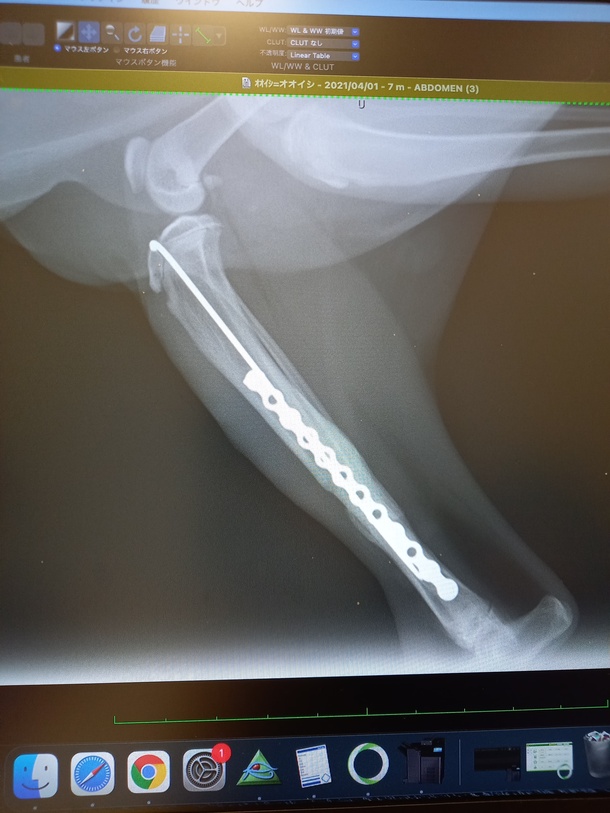

くっついた!!

骨も無事再生してきました。

順調順調☺️